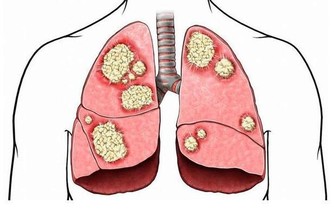

另外體內的膽汁及毒素變的更加容易循環原因是因脾臟位於身體的左側。

脾臟是身體最大的淋巴器官,流動的方式是靠著肌肉收縮,如果不往左側睡淋巴會停擺,因此靠左側睡淋巴液會因重力流入脾臟,循環更加有效率也能幫助毒素排出。